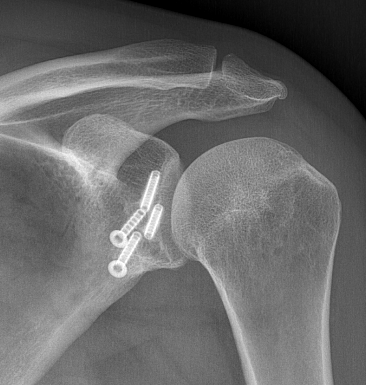

Bone block positioning

Concepts

- coracoid must not overhang medial to avoid osteoarthritis

- coracoid < 5 mm medial to glenoid rim

- coracoid lower half of glenoid 2 - 5 o'clock

- fixation screws purchases posterior glenoid cortex

- screws do not penetrate articular surface

Secure coracoid

- inferior half of glenoid

- no medial overhang

- secure with 2 x bicortical screws with compression